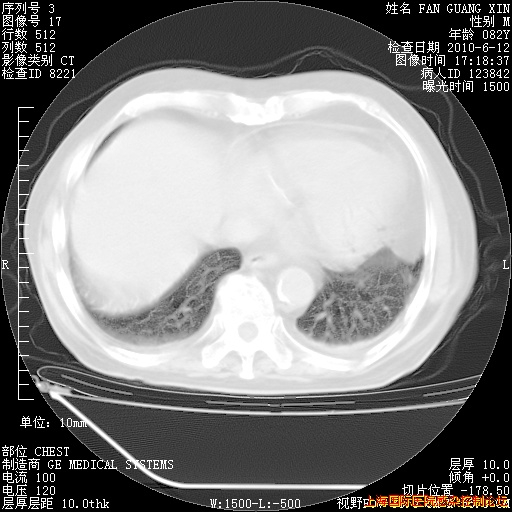

6月12日纵膈窗

整整相隔30天的肺部CT好像有所好转啊。甲强龙减量第3天,需要观察体温。

海管,自昨日你和我通完话后,不知您岳父消化道症状有无缓解?体温怎样?阅读7.12日胸部ct,个人认为目前激素治疗是有效的,甲强龙减量是适宜的。因在抗痨治疗,需密切观察肝功、肾功能和血常规。不过,老年、长期住院和大量使用激素,很担心菌群失调发生